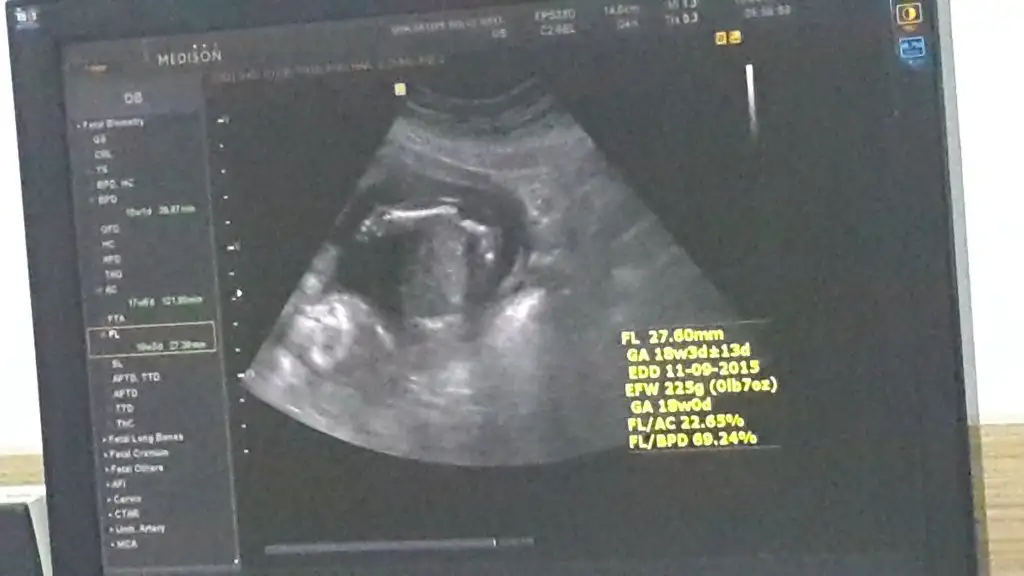

dr soylemeden siz gorun genital nub teorisi ( bebegin cinsiyeti)

Benim bebeğimin cinsiyeti konusundada bana yardımcı olabilirseniz çok sevinirim hanımlar :)

Bu bebiste erkek gibi geldi bana dikkatli bakinca cikinti var yukari kalkik paralel deil.. kac hagtalik sen ne hissediyorsun ??? Doktor hicmi yorum yapmadi

23 bitececek ccnm kizsada erkek sede benim hayatim o ama bir kesinlesmedi dunde erkek gibi dedi